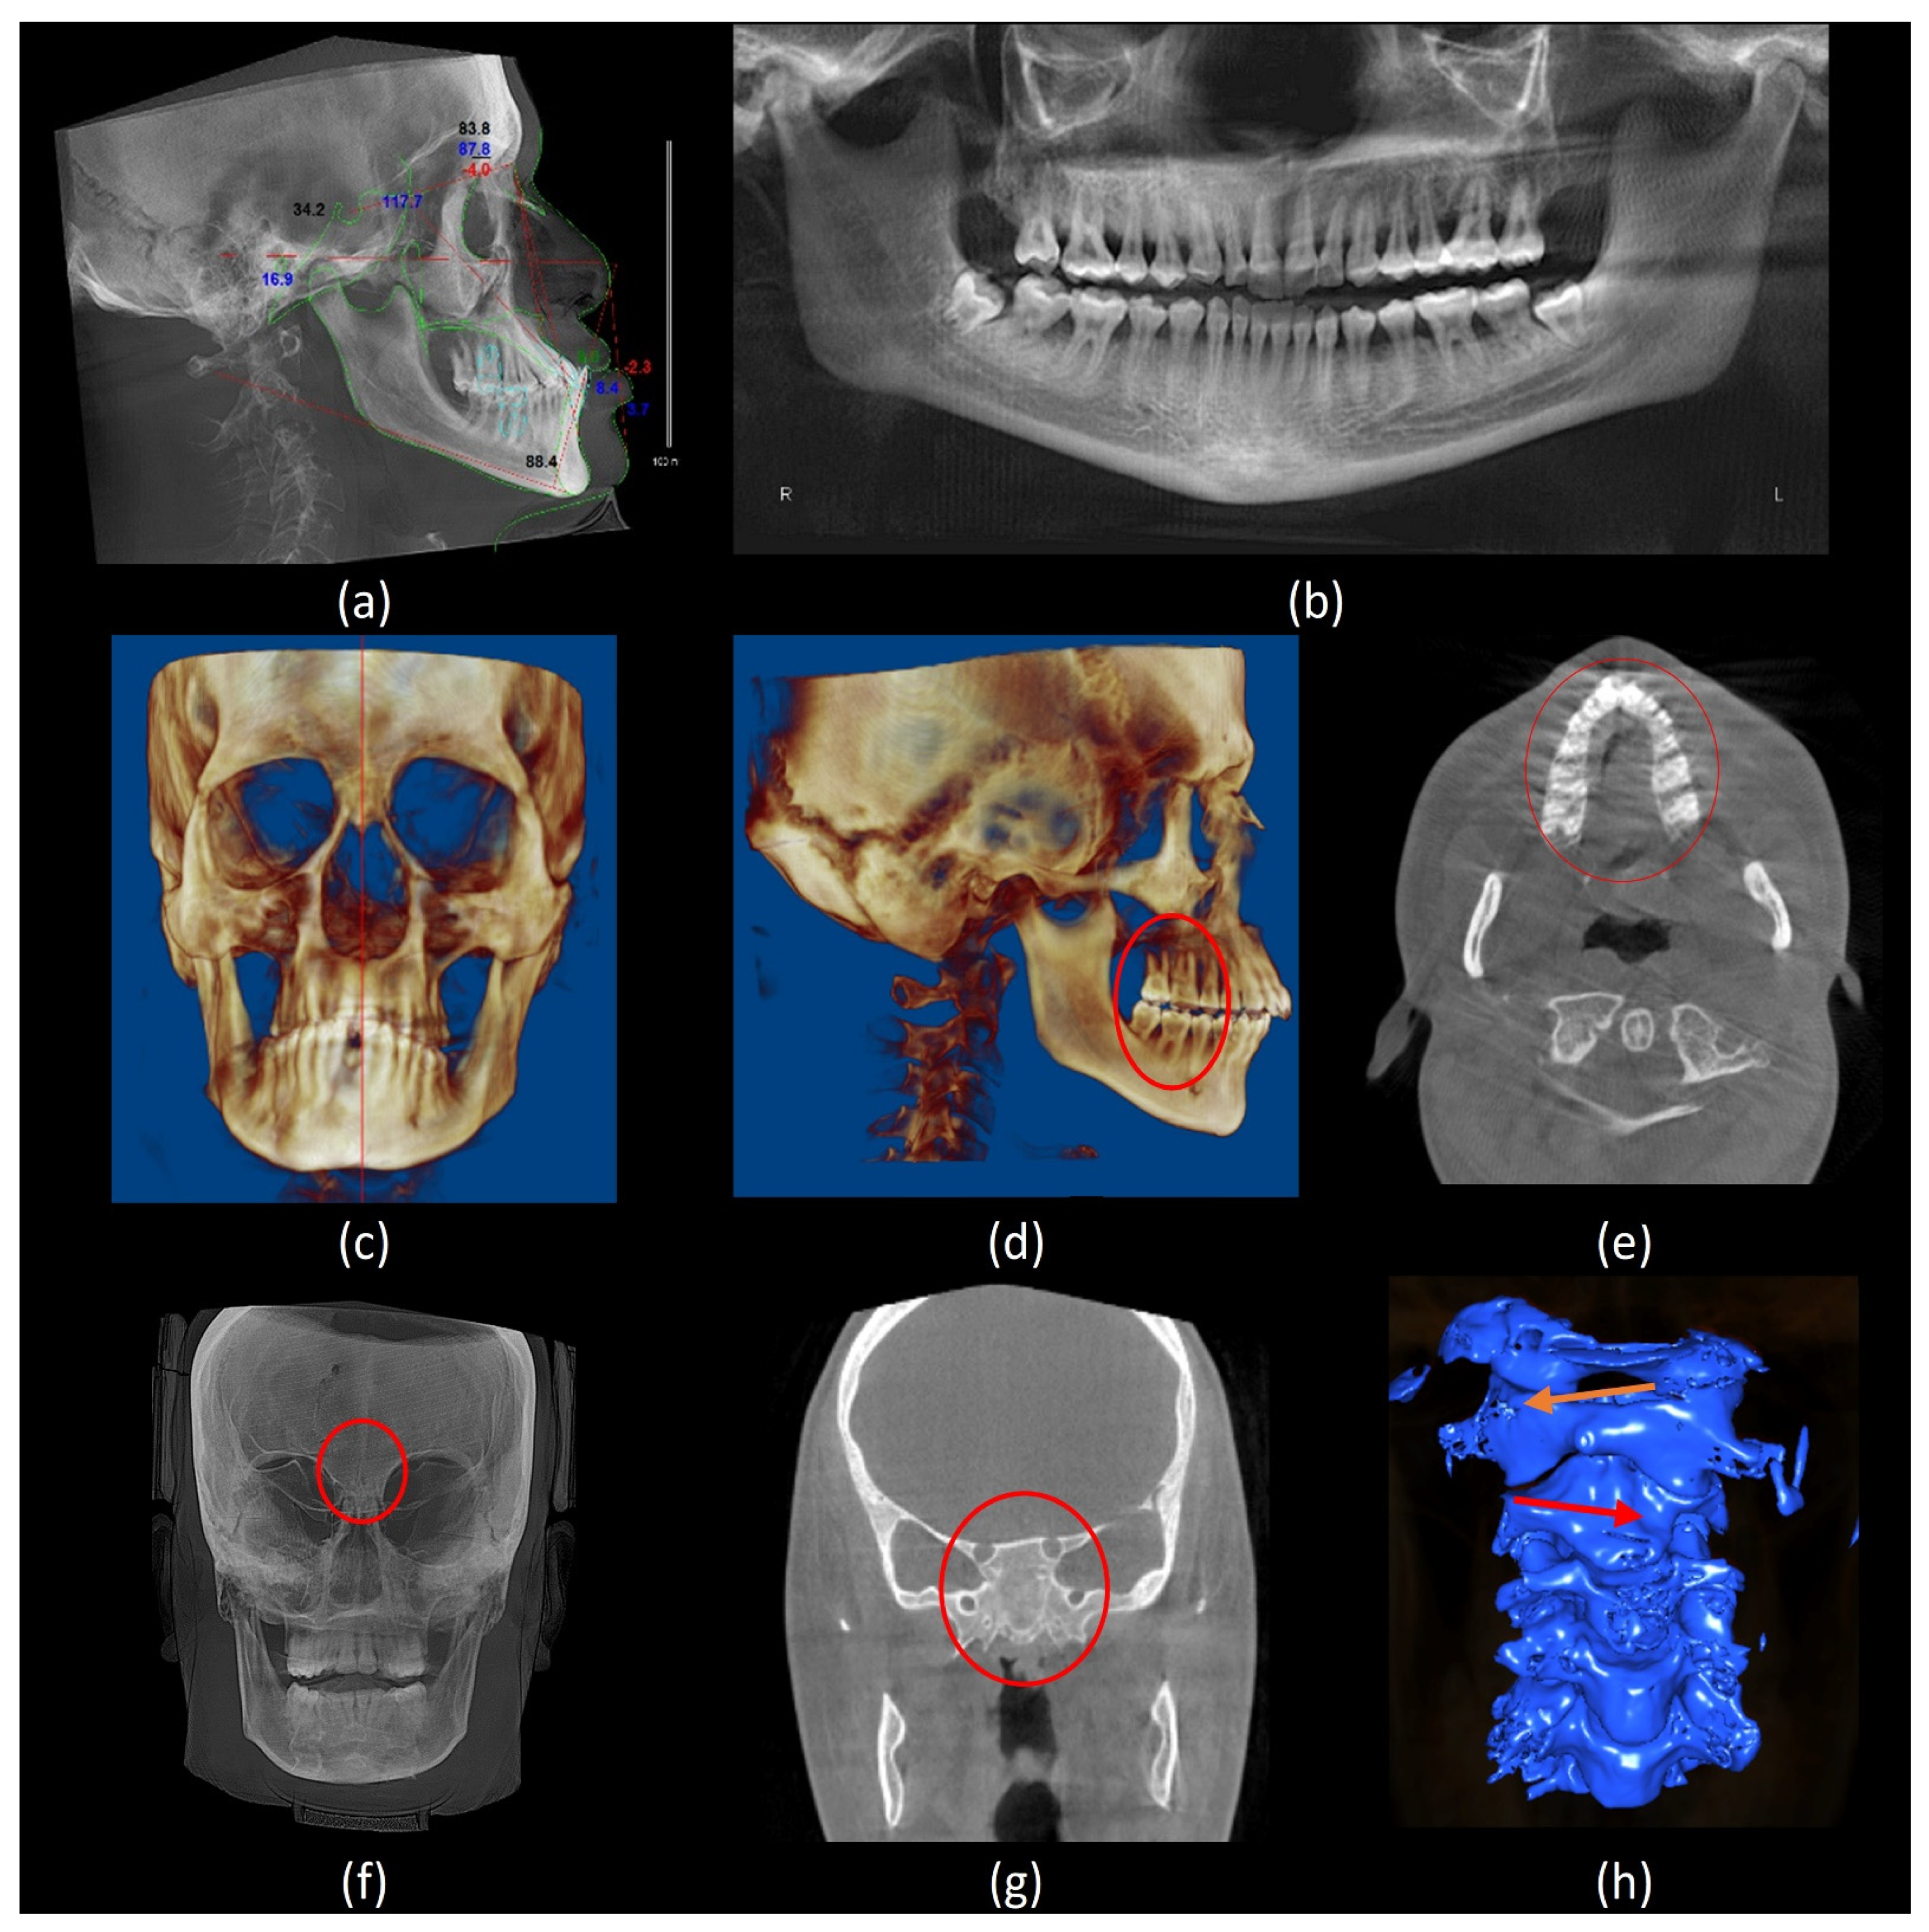

Figure 4.

Various radiographic findings. (a) A lateral cephalometric analysis shows hypodivergent face type, hypoplastic maxilla, proclined anterior teeth, and anterior crossbite; (b) a panoramic reconstruction view shows a periodontal bone loss, impacted mandibular third molars and hypoplastic maxillary sinuses; (c) a 3D frontal volumetric rendering view shows facial asymmetry; (d) a 3D lateral volumetric rendering view shows Class II skeletal pattern (prognathic maxilla and orthognathic mandible) Molar class II full step (red circle); (e) an axial CBCT slice shows hypoplastic maxilla (red circle); (f) a frontal view of maximum intensity projection (MIP) shows aplastic frontal sinuses (red circle); (g) a coronal CBCT slice shows aplastic sphenoid sinuses (red circle); and (h) a 3D segmentation model of the cervical spine shows an anticlockwise-rotated C1 vertebra (orange arrow), accompanied by clockwise-rotated C2 and C3 vertebrae (red arrow).